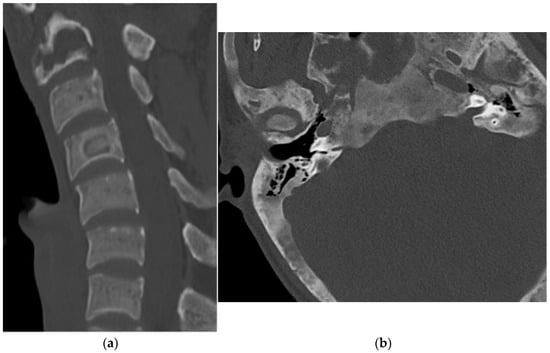

2.2.1. Osteochondroma

2.2.2. Chondroblastoma